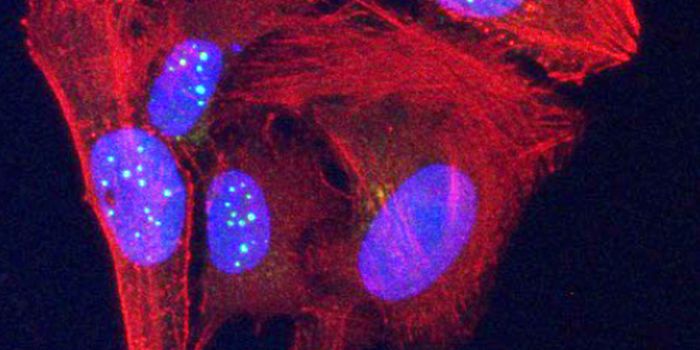

FEB 21, 2023Cell & Molecular BiologyThe Griffith Lab at UNC discovered telomeric protein & potential biomarker VR (green), shown in the nuclei (blue) of hum ...

AUG 31, 2021Clinical & Molecular DXCellular stains are organic fluorescent dyes or fluorescent conjugates designed to localize to a specific organelle or c ...